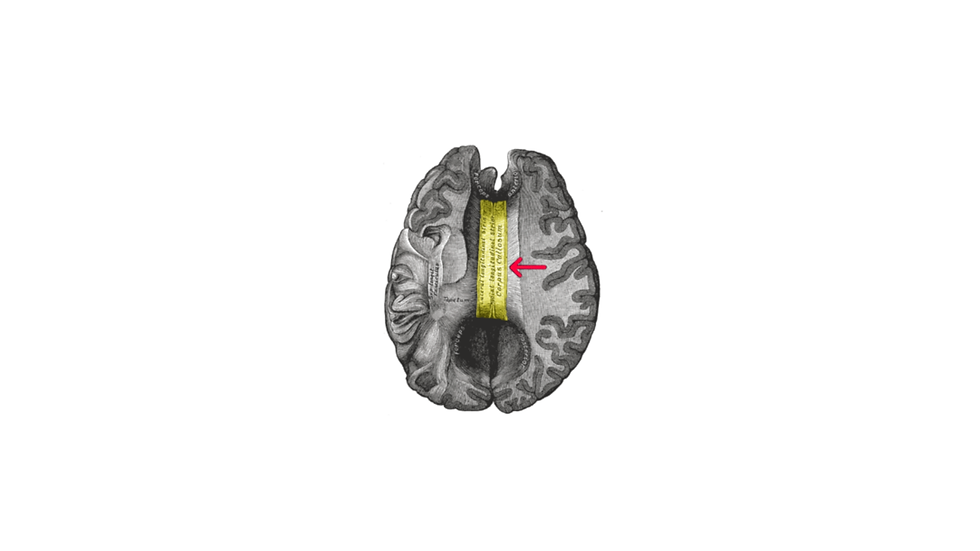

Back in the 1940s, for intractable forms of epilepsy, a surgical procedure was developed to “split” the brain by cutting the corpus callosum, a wide bundle of nerves connecting the two cerebral hemispheres. In addition to the procedure reducing or stopping seizures in most patients, while seemingly retaining normal function, the split-brain patients provided an opportunity to study lateralization of brain processes.

It has been shown that specific functions like language, handedness and facial recognition, among others, are specialised in one of the hemispheres (Though there are many caveats like individual variability as well as myths and oversimplifications associated with left-right hemisphere lateralization – see Ana and Pascal’s previous article andThe Lateralized Brain for a review). The language centre is generally in the left hemisphere, while each hand is generally controlled by the opposing hemisphere.

In a split-brain patient, because their corpus callosum is cut, functions carried out by one side of the brain cannot be communicated to the other. So, information in the right hemisphere cannot reach the language centre in the left. In the 1970s, when the modern era of split-brain research began, neuroscientist Michael Gazzaniga (and his research team) wondered what would happen if information was sneaked into the right hemisphere of split-brain patients.

Using a set up where the split-brain patient would focus on a point on a screen, images can be fed to either side of the brain when placed adjacent to that point (see figure below).